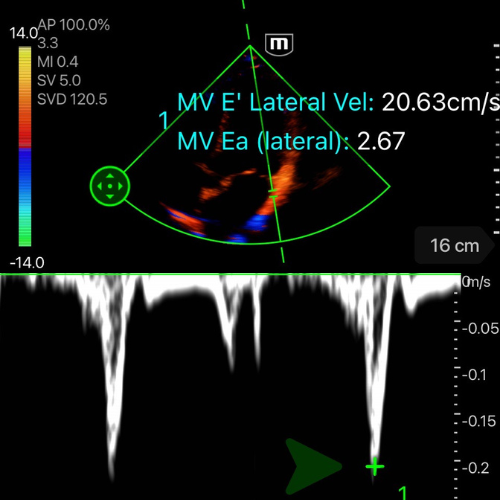

🔧 Comment mesurer E/E’

- Mesurer l’onde E comme décrit ci-dessus (si déja fait, la machine retient la valeur)

- En A4C, placer le curseur sur l’anneau mitral, en latéral

- Activer le mode Doppler tissulaire (TDI).

- Chercher la premiere onde négative apres le onde S' – c'est l'onde E’ (cf. vidéo/photo ci-dessous)

- Mesurer la vitesse maximale de E’. La machine fait le calcul du rapport pour vous.

-

E/E’ < 8, PRVG basses : le cœur tolérera un remplissage, et une hypovolémie est possible.

E/E’ > 14, PRVG hautes : tout apport hydrique risque d’aggraver la congestion ou de précipiter un œdème pulmonaire.

E/E’ 8–14, zone grise : l’interprétation dépend du contexte (tachycardie, sepsis, IC chronique, ventilation mécanique). Le chiffre seul ne suffit pas à guider la prise en charge.

![]()